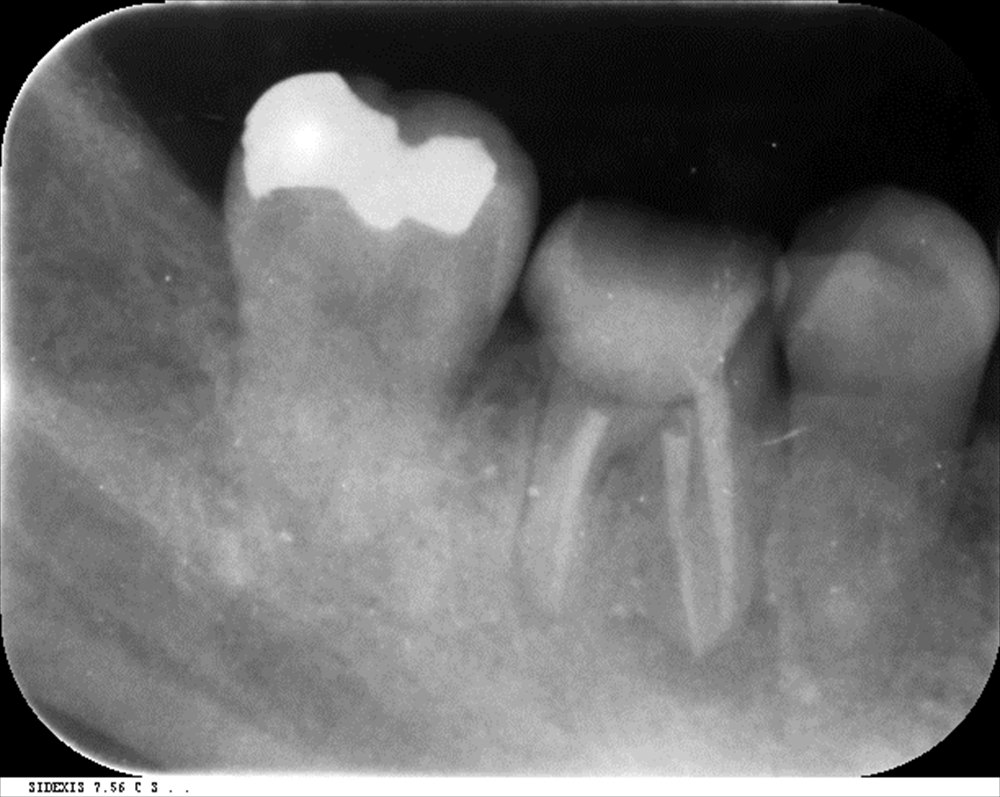

この右下6番。顔まで腫れている状態。根尖病変が大きく骨を溶かして歯茎を突き破っている状態。痛くて寝れない。。。抜いちゃえば早いですが抜きません。

石灰化も見られ難易度は高いです。湾曲もあります。

前医の先生も「石灰化が強いからここまでしかお薬を入れられない。次何かあれば抜歯してインプラント」と説明があったそうです。石灰化してその下に病変があるということは何が何でもセンツウさせるかOPEか。ということになります。

マイクロスコープで根管を探しセンツウ!成功

3回で根管充填

DB根はMTAで根管充填。後はガッタパーチャで。